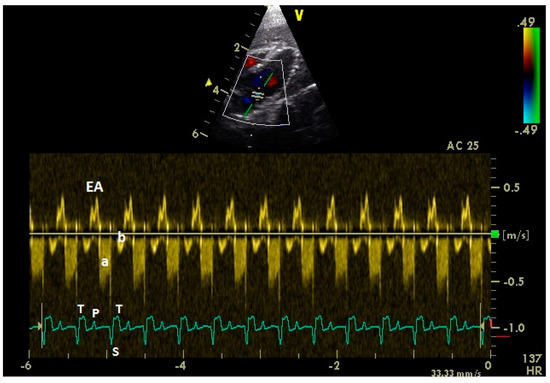

3.1. Diastolic Ventricular Filling Blood Flow Velocities in Conscious Racing Pigeons

3.4. Examination of the Diastolic Blood Flow with Color Doppler Flow Imaging